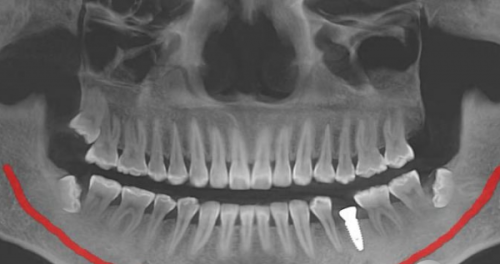

除了价格透明,正规牙科在设备和服务上也不断升级。现在很多机构都配备的口腔扫描仪和成像设备,能更发现牙齿问题。补牙过程中也会严格遵循无菌操作,一人一机一消毒的安心服务。补牙完成后,医生还会耐心交待注意事项,帮助患者更好进行术后维护。